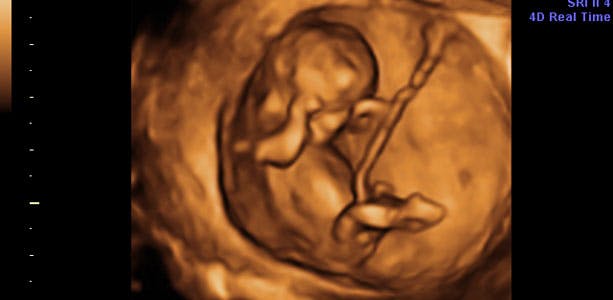

Gravid uge 11: Kvalmen aftager

Hovedet er næsten lige så stort som resten af kroppen. Leveren er stor og fylder det meste af bughulen. Tarmene er der ikke plads til endnu. Derfor er de snoet ud i navlesnoren. Dette kan af og til ses på ultralydsscanning som "fysiologisk navlebrok", der ses som en udbuling på navlesnoren. Hjertet slår med cirka 110-160 slag pr. minut. Sidst på ugen måler dit barn cirka 45 millimeter fra hoved til hale.